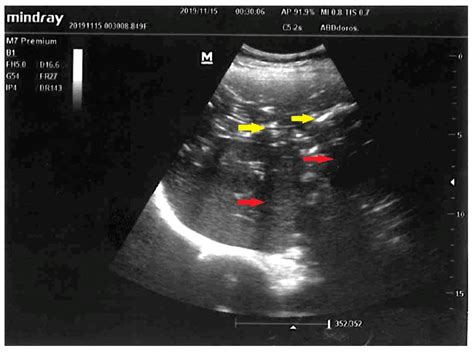

The gold standard for detecting portal venous gas is a CT scan of the abdomen, usually with intravenous contrast. On a scan, gas appears as low-attenuation, branching, linear lucencies that extend into the periphery of the liver. This pattern is distinct from pneumobilia (gas in the bile ducts), which typically resides in the central portion of the liver and follows the path of the biliary tree.

Distribution Extends to the liver periphery Central, follows biliary tree

Morphology Branching, thin lucencies More rounded, central